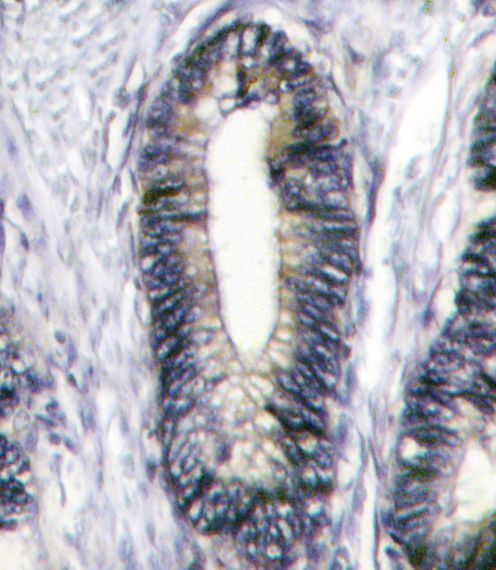

Applikationen WB, IF, IHC-P

IHC-P: 1:10~50